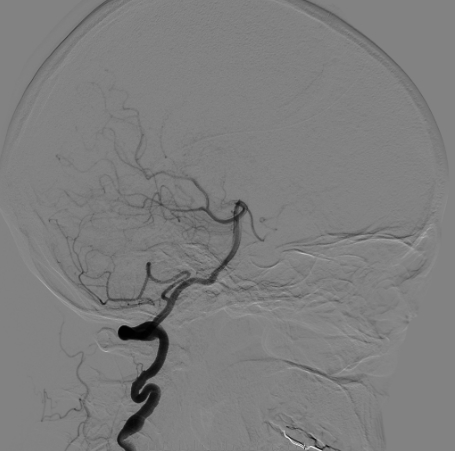

支架部分释放后复查造影示支架位置良好,缓慢完全释放支架,支架打开良好,复查造影示支架位置良好,完全覆盖瘤颈,贴壁佳,瘤囊内可见造影剂滞留明显,OKM分级A3。

Vaso CT显示 畅医达(Choydar)血流导向装置 位置良好,完全覆盖瘤颈,长轴及横轴薄层均显示支架贴壁良好。

术后即刻正侧位造影显示载瘤动脉及远端分支显影无异常,瘤囊内可见明显造影剂滞留;Xper-CT未见出血。